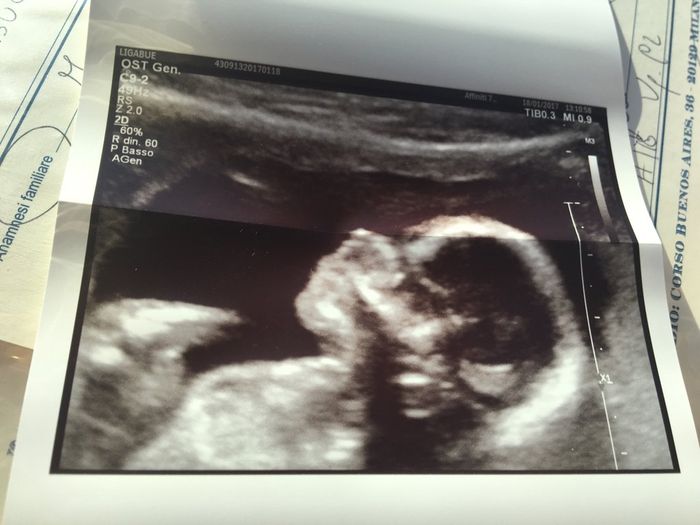

Oggi abbiamo fatto la pre morfologica! Il cucciolo sta benissimo è lungo 15 cm per 160 grammi.. si muoveva tantissimo! Il sesso cel'aveva già detto al bi test ma oggi volevamo conferma ma il monello ha tenuto le gambine complemetamente chiuse...